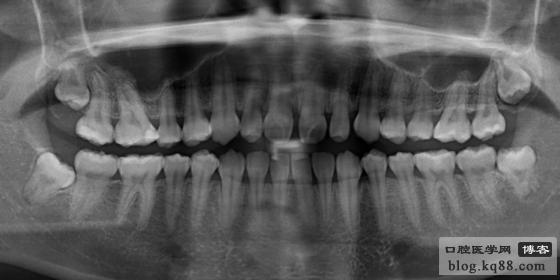

X線片檢查無多生牙